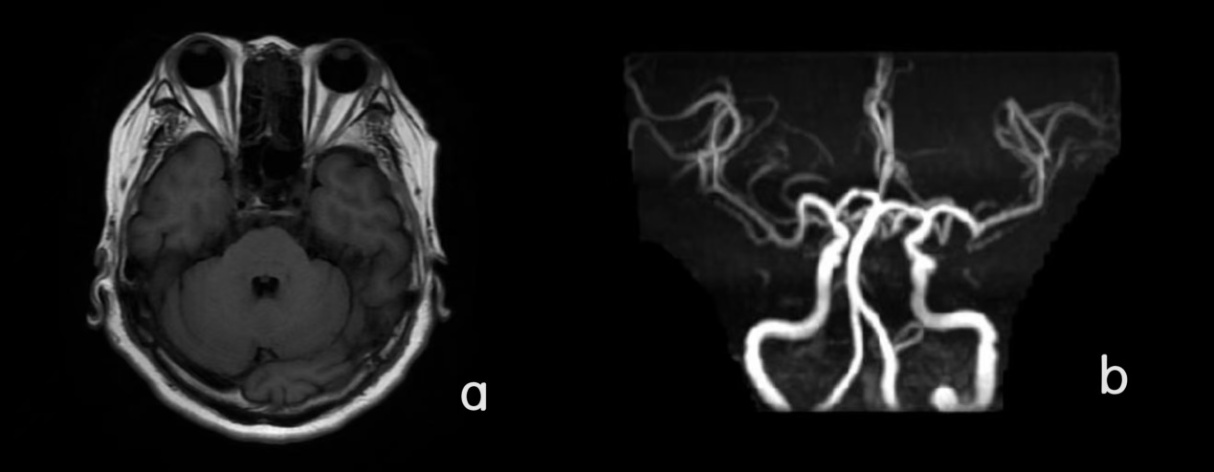

4、相关检查:磁共振颅脑平扫 + DWI (如图1):1) 缺血性脑白质病变(改良Fazekas1级),请结合临床随诊。2) 部分副鼻窦炎。磁共振颅脑动脉(MRA) (如图1):1) 头颅MRA符合脑动脉硬化表现。2) 左侧大脑后动脉P2段局限性狭窄,必要时进一步检查。3) 基底动脉走行略延长。超声心动图:左房饱满,室间隔基底段轻厚,肺动脉轻宽,左室舒张功能减低、收缩功能未见明显异常,右心功能未见明显异常。

Figure 1. (a) Plain scan of brain MRI; (b) MRA of brain

1. (a) 颅脑核磁平扫;(b) 颅脑MRA